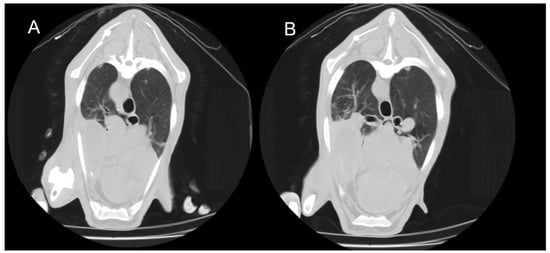

3.3.1. Interstitial Pneumonia (SRLV)

3.3.2. Gangrenous Pneumonia (GN)